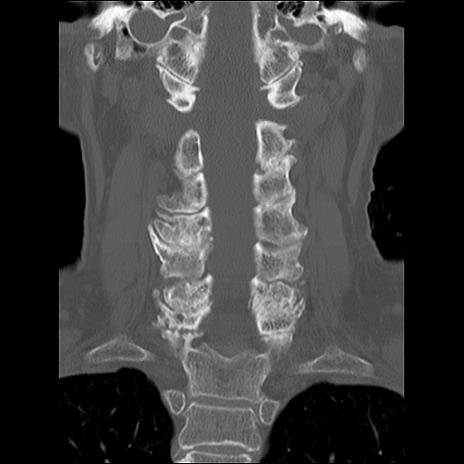

症例48 頚椎CT(冠状断像)

頚椎CT